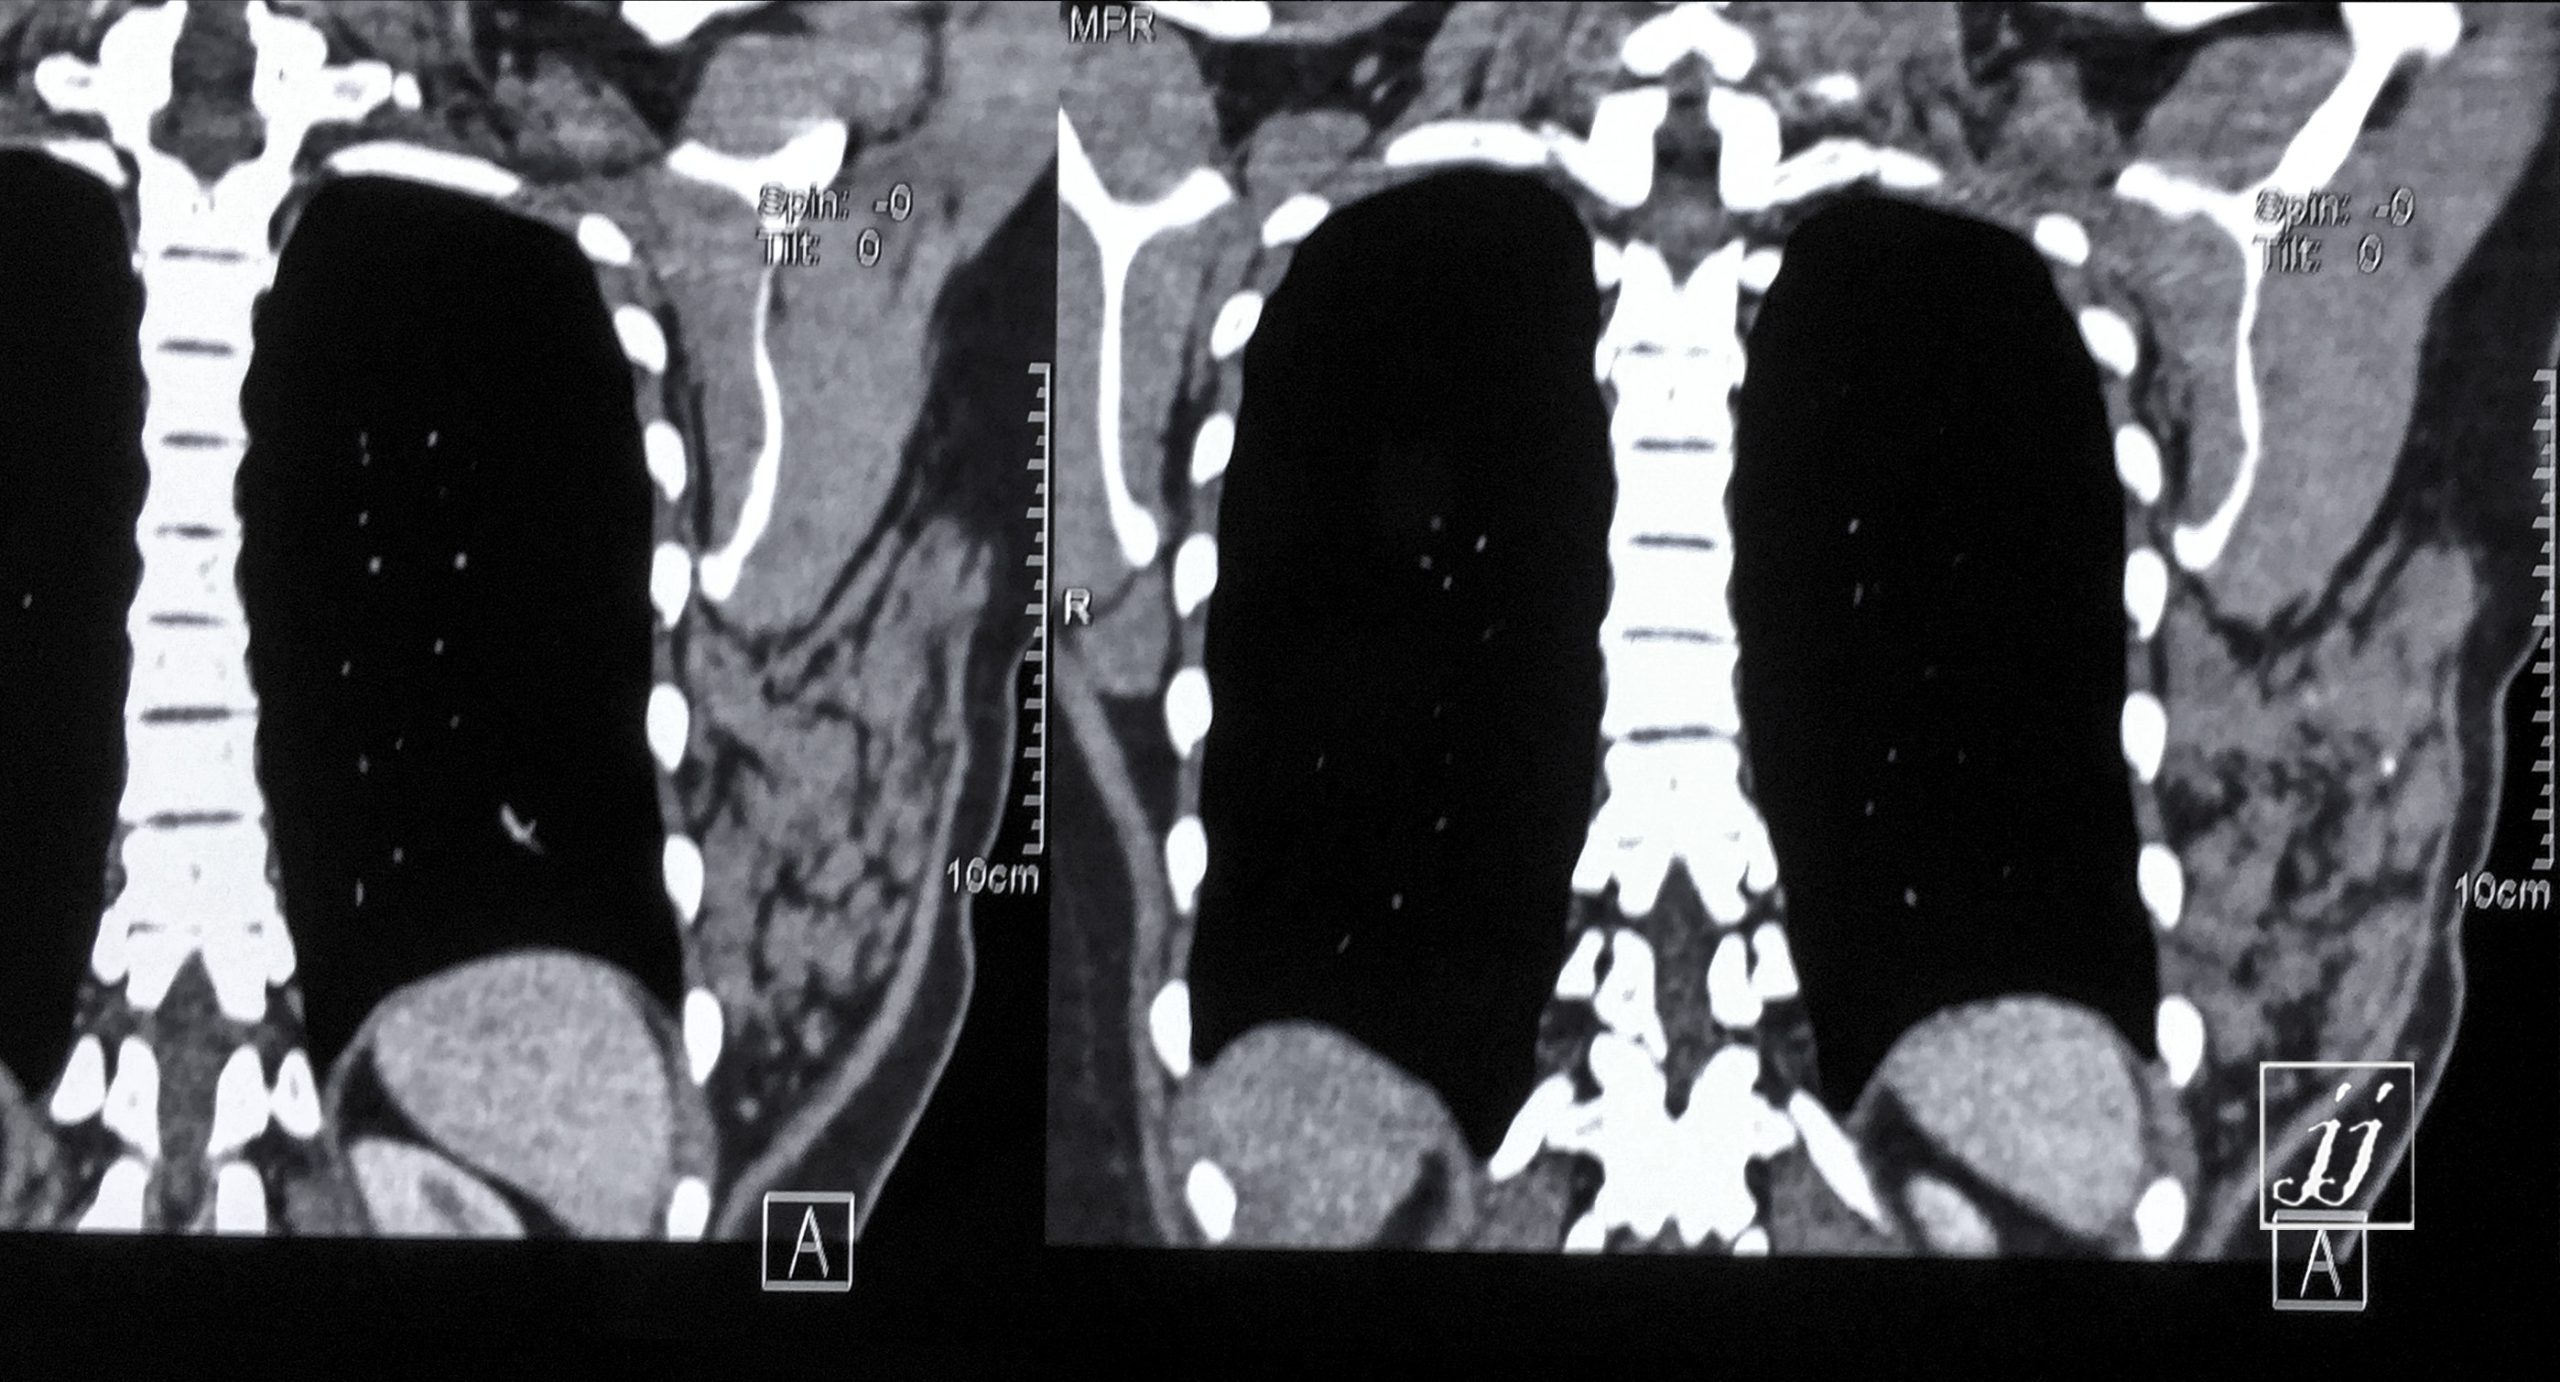

Chest- left rib cage fracture (9)